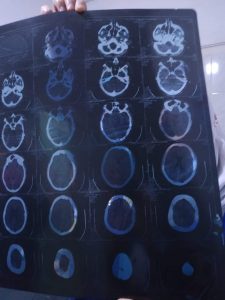

بتوجيه من الدكتور هشام شوقي مسعود وكيل وزارة الصحة بالشرقية برفع كفاءة الخدمات الطبية المقدمة للمرضي بمستشفيات الصحة، قام الفريق الطبي بقسم جراحة الوجة والفكين بمستشفي فاقوس النموذجى أمس الأثنين 22/3/2021 بمشاركة د. محمد عبد الرحمن سعد رئيس قسم جراحة الفم والأسنان، ود. محمد حلمي إبراهيم أخصائي جراحة الفم والأسنان، ود. عماد عبد القادر عليوه طبيب التخدير، وفنيين الأشعة، وهيئة تمريض العمليات بالمستشفي، بإجراء عملية جراحية دقيقة وعاجلة بالوجه والفكين لحالة حرجة، تبلغ من العمر ١٨ عام، وتعاني من كسر مفتت بالفك السفلي جهة اليمين، وذلك بعد إجراء الفحوصات والأشعة اللازمة، حيث قام الفريق الطبي بإجراء تثبيت الكسر بالشرائح والمسامير الجراحية، والحالة الآن مستقرة وتحت الملاحظة الطبية، بإشراف مدير المستشفي.